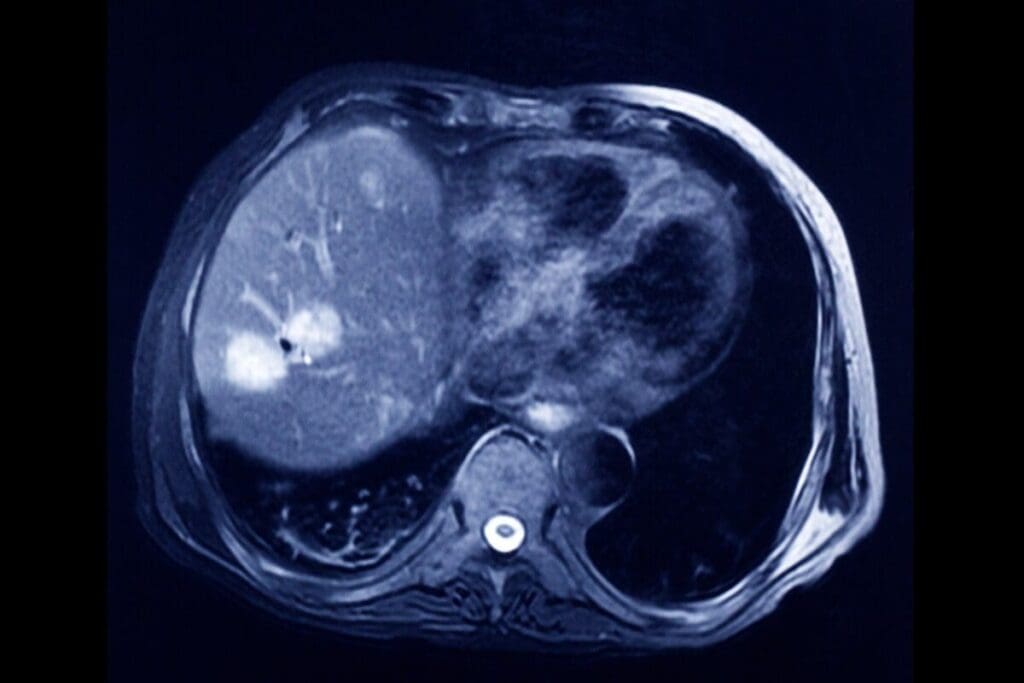

Alternative Imaging Techniques

Other imaging methods, like MRI, ultrasound, and PET scans, can also help find and check bladder cancer. MRI, for example, shows soft tissues well and helps see how far a tumor has spread.

Each imaging method has its own good points. Doctors pick the best one based on the patient’s needs and the tumor’s type.